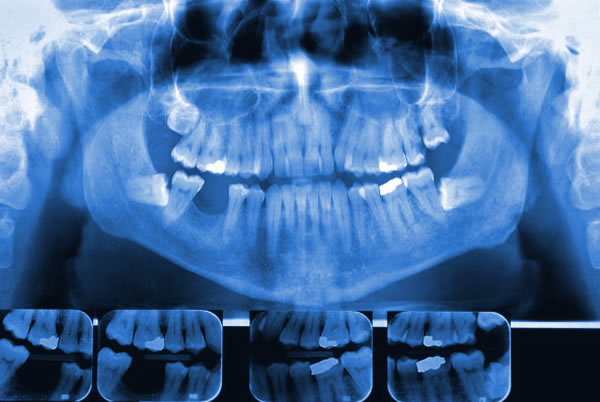

Nos foros criminais, atua quando se trata de identificação de pessoas, identificação da espécie animal, determinação da morte, prova de virgindade ou conjunção carnal, diagnóstico de lesões corporais e dos instrumentos ou meios que as causaram, apreciação do estado mental do criminoso ou da vítima etc.